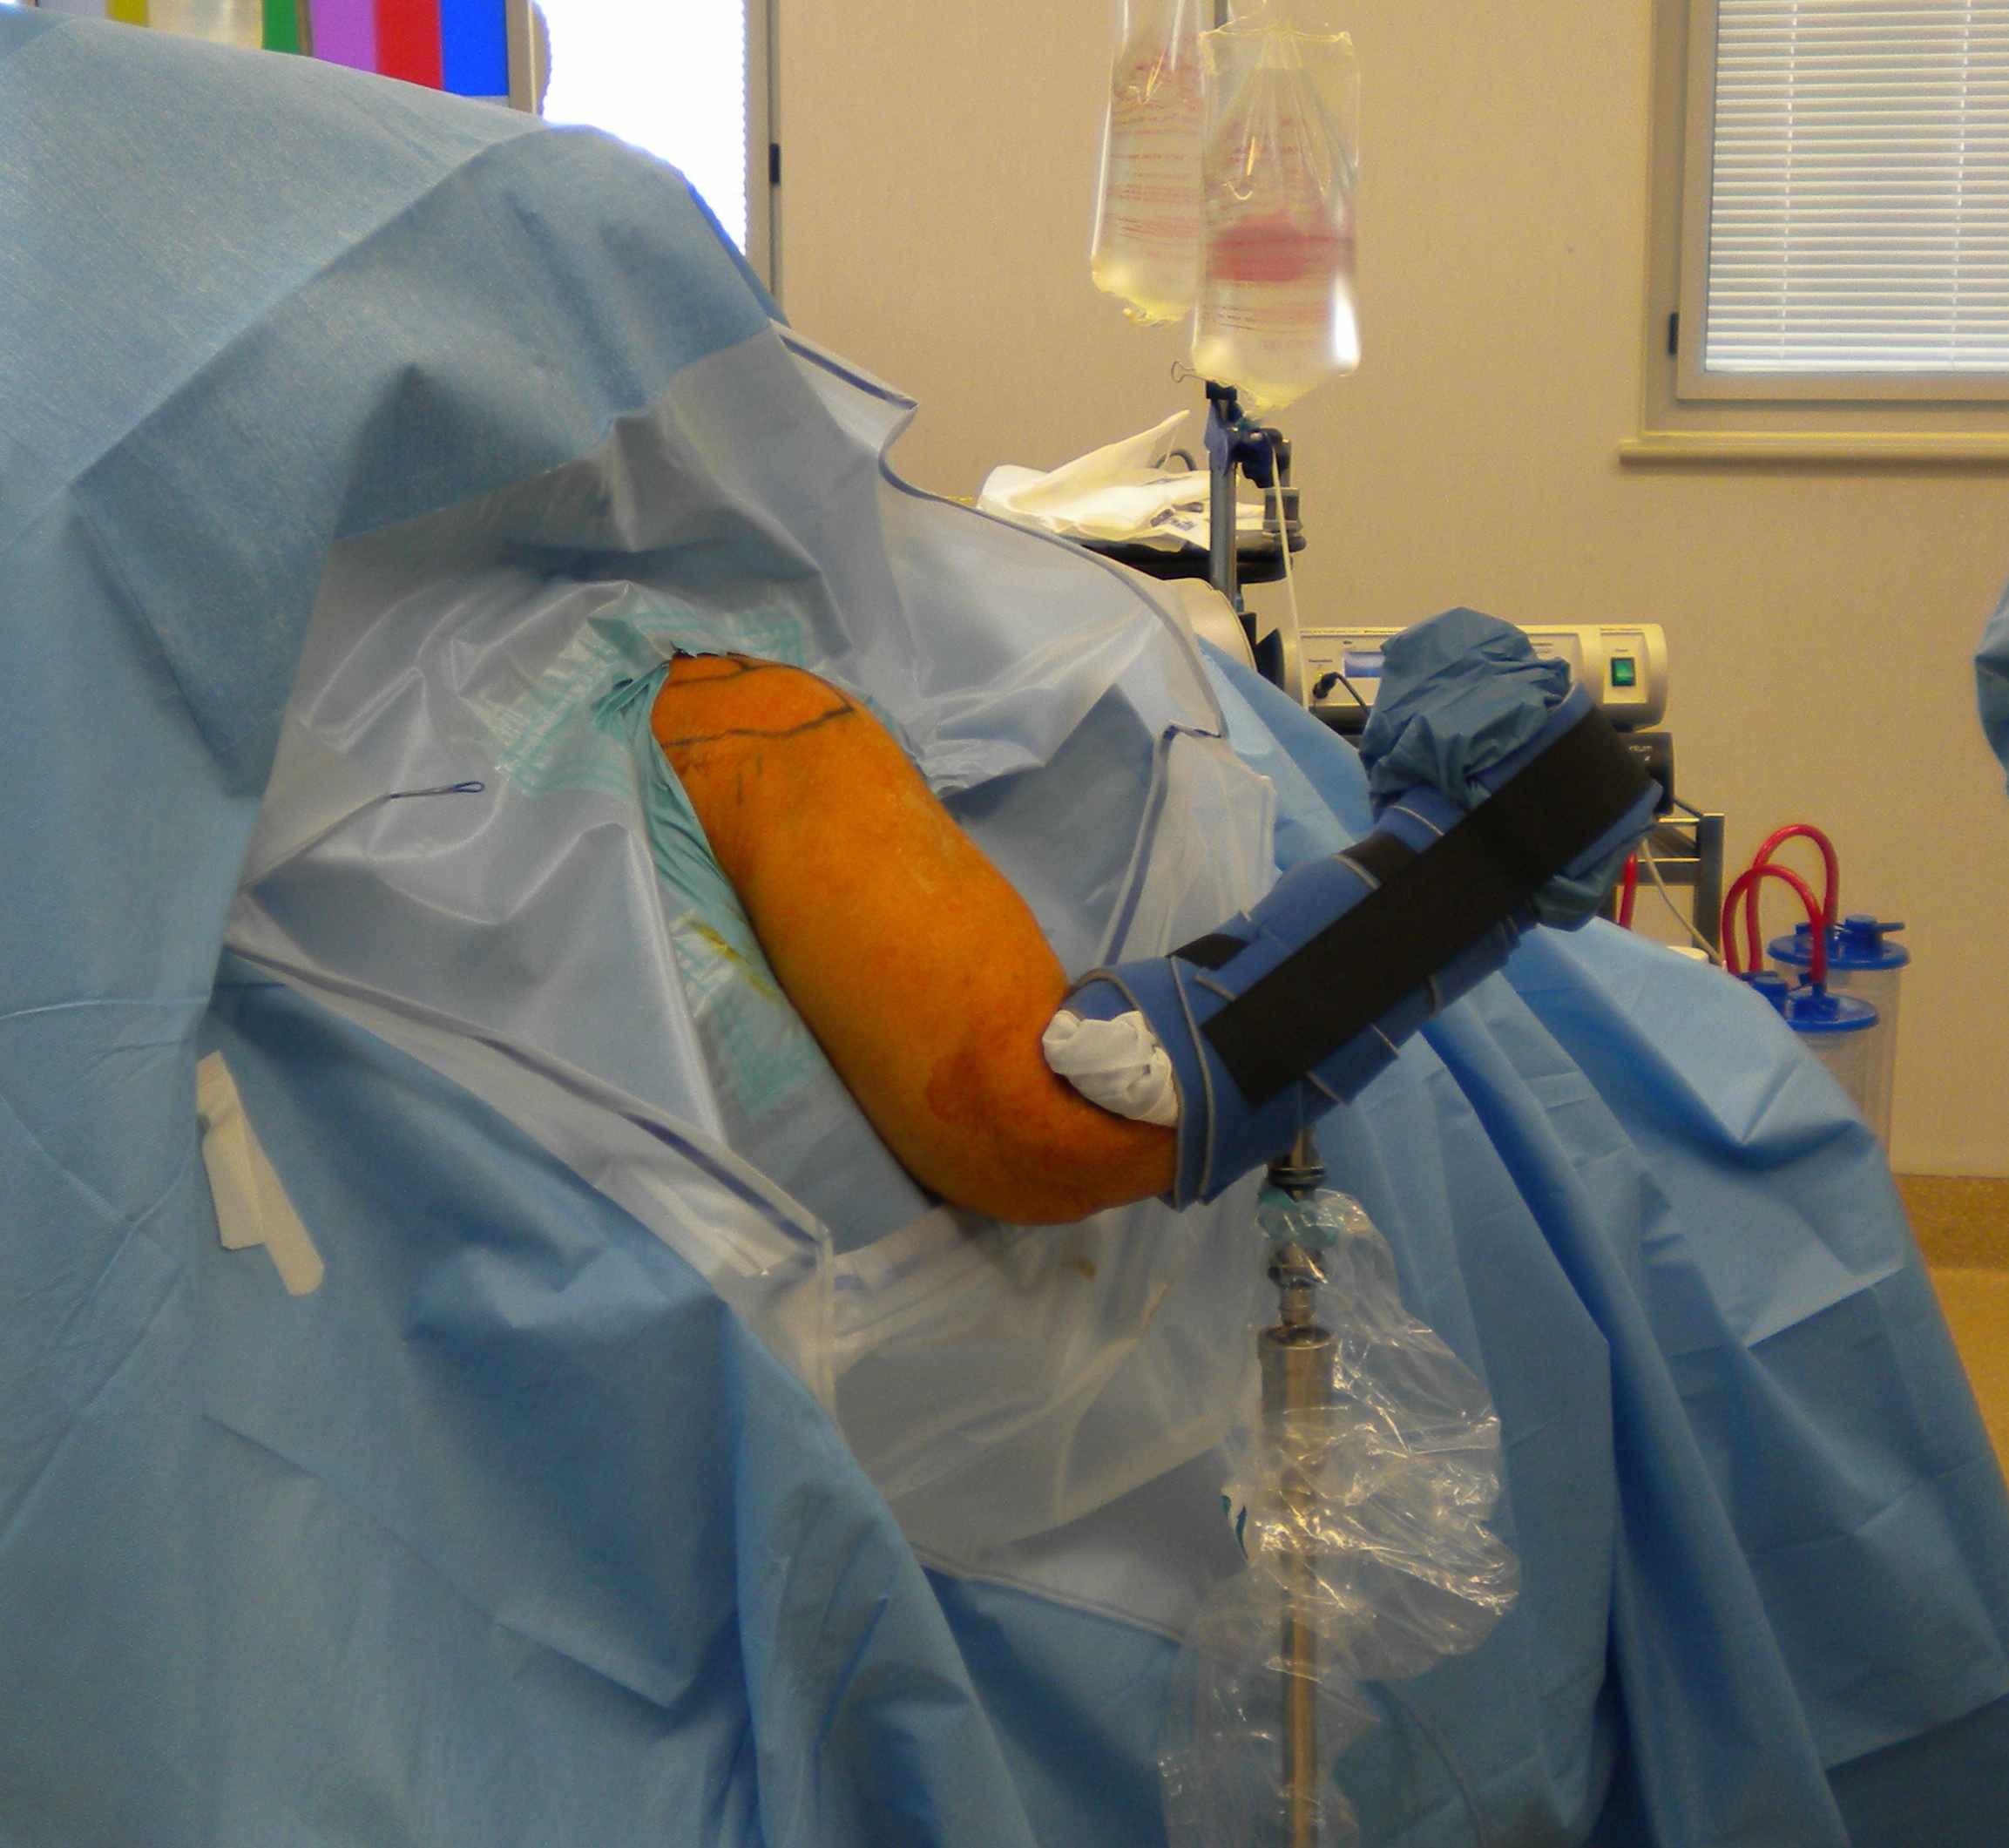

Position

| Beach chair | Lateral decubitus |

|---|---|

| Patient seated upright | Patient on side in beanbag / lateral supports |

| Head attached / protect eyes / neck in normal position | Skin traction to forearm with traction pole / lateral support |

| Arm free draped on mayo / hydraulic arm holder | Arm abducted / lateral traction to glenohumeral joint |